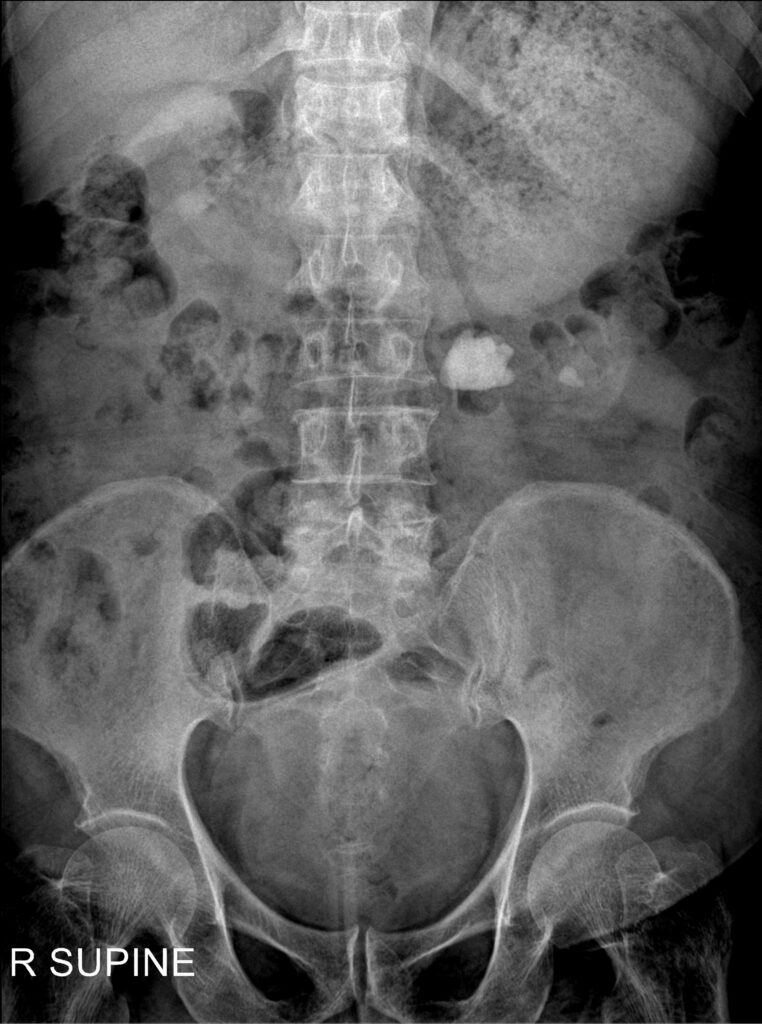

DIAGNOSIS: Advanced Imaging for Kidney Stones in DFW

Accurate diagnosis ensures proper treatment. Dr. Bevan-Thomas recommends advanced CT imaging to determine the precise size, type, and location of each stone. Follow-up X-rays, such as a KUB, are excellent to evaluate treatment results.

Diagnostic tools include:

- CT Scan: The gold standard for detecting even tiny stones, which guides the choice between ESWL, CULLS, or PCNL.

- KUB X-ray: Used to track the progress of calcium-based stones as they pass or after treatment.